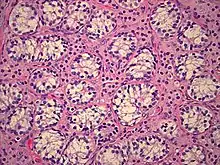

![]() | |

| AIS results when the function of the androgen receptor (AR) is impaired. The AR protein (pictured) mediates the effects of androgens in the human body. | |